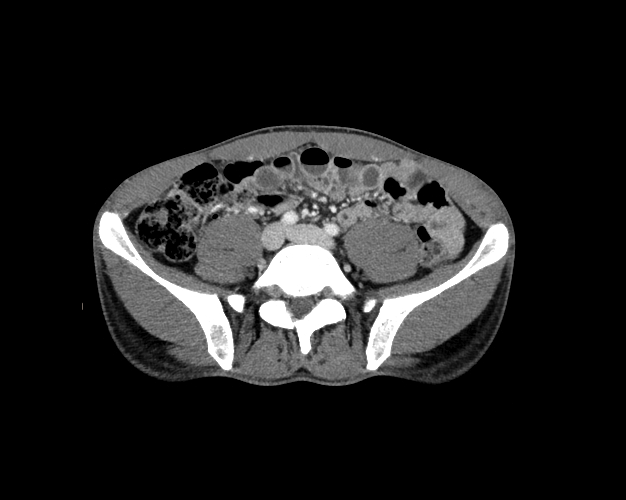

Body

Covers abdominal CT anatomy.